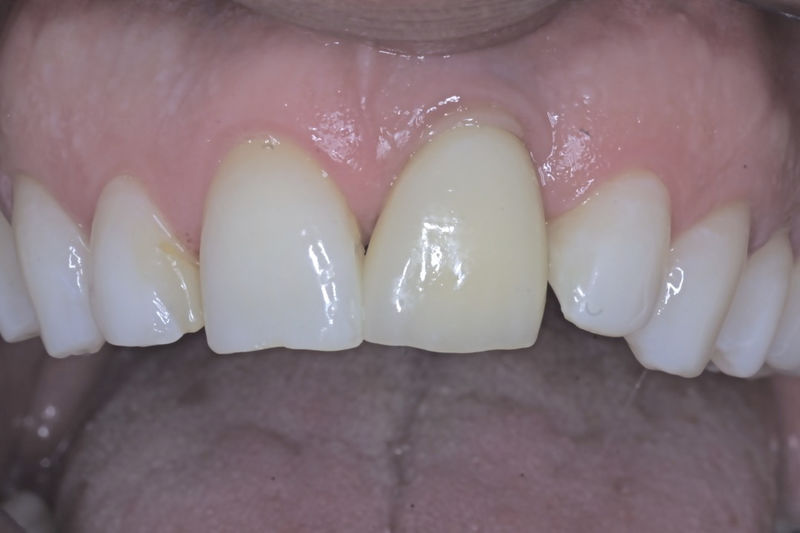

Son restauraciones que cubren toda la cara frontal del diente, generalmente empleadas en el sector anterior y cuya finalidad es primariamente estética.

Restauraciones fabricadas en el laboratorio con materiales estéticos, los cuales cubren de manera total dientes anteriores y posteriores. Se utilizan primariamente para restaurar dientes con caries, fracturas y/o defectos amplios, así como soportes de puentes. Para poder enviar el caso al laboratorio se toman impresiones utilizando materiales de impresión o técnicas modernas digitales.